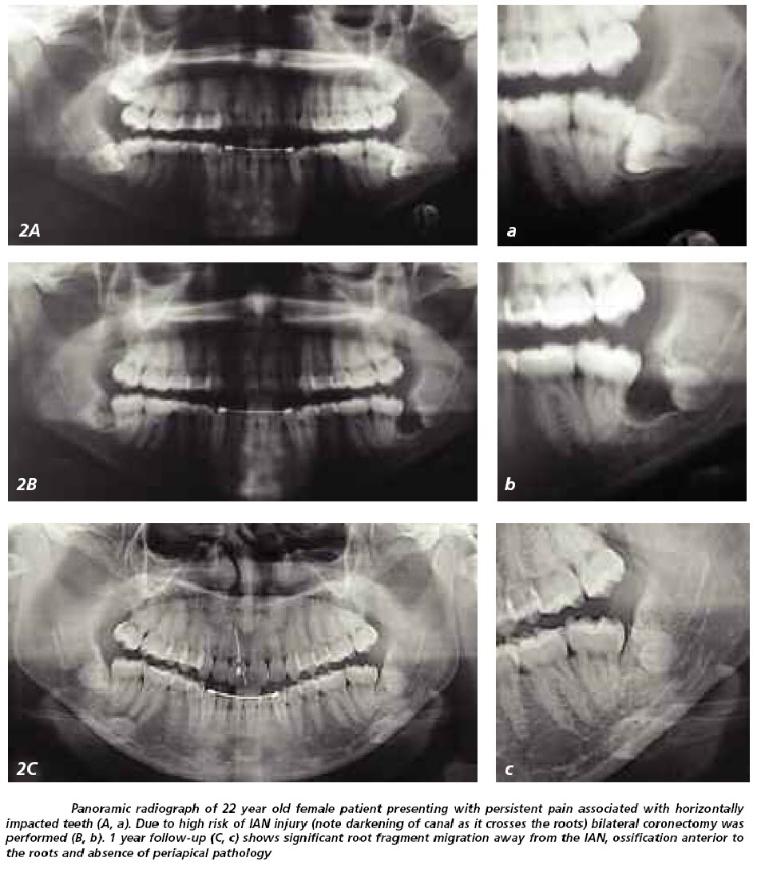

Root Migration.

Subsequent migration of the roots away from the IAN occurred in 14 – 81% of cases. The roots seem to move the most during the first 6 months post-coronectomy, with a typical distance of 2 – 3mm away from the IAN. Root migration halts as the bone regenerates and remodels.

Later Removal of Roots.

This can happen in up to a 2 – 6% of cases. If the roots irritate overlying tissues or the adjacent tooth or otherwise become symptomatic, they may need to be removed. Even though a 2nd surgery would be needed, the possibility of nerve damage should be negligible since the roots would have migrated away from its original resting place next to the IAN. Since the purpose of the coronectomy is to avoid this damage, this goal would have been accomplished even though a 2nd surgical procedure was necessary to remove the remaining root.